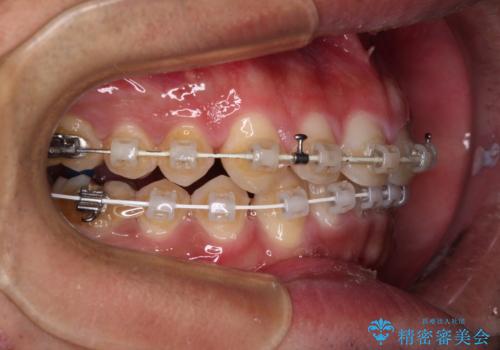

深い咬み合わせと隙間の空いた歯列をワイヤー矯正で改善

- 前歯の隙間と深い咬み合わせを改善したいとのことで来院された患者様です。

マウスピース矯正の自己管理が面倒とのことで、ワイヤー矯正により治療を行うこととしました。

奥歯の咬み合わせは理想的な状態であったため、ワイヤー矯正でもインビザラインでも比較的容易に対応可能でした。